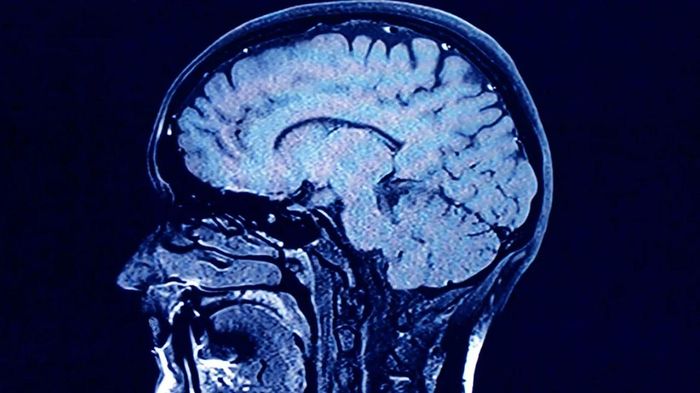

Các nhà nghiên cứu đang khám phá về quá trình lão hóa của não bộ con người, đồng thời những cách thức để bảo vệ sức khỏe não bộ, bao gồm việc tập thể dục, không hút thuốc, học ngôn ngữ mới và chơi nhạc cụ.

Một nghiên cứu được công bố trên tạp chí Genomic Psychiatry cho thấy rằng khả năng tư duy và ghi nhớ của người già có thể liên quan đến thành tích học tập của họ khi còn nhỏ, khoảng 11 tuổi.

Bài viết, dựa trên dữ liệu từ các nghiên cứu của Lothian Birth Cohorts tại Scotland, cho thấy một nửa lý do tại sao một số người già nhớ tốt, còn một số khác lại quên nhiều, có thể là do khả năng tư duy của họ đã được hình thành từ thời thơ ấu.

Tuy nhiên, một số yếu tố trong lối sống của người trưởng thành dường như vẫn có mối liên hệ với việc cải thiện chất lượng và làm chậm quá trình lão hóa của não.

Các nhà nghiên cứu phát hiện ra rằng cả yếu tố di truyền và lối sống đều có thể ảnh hưởng đến quá trình lão hóa của não bộ. Ảnh: Getty Images